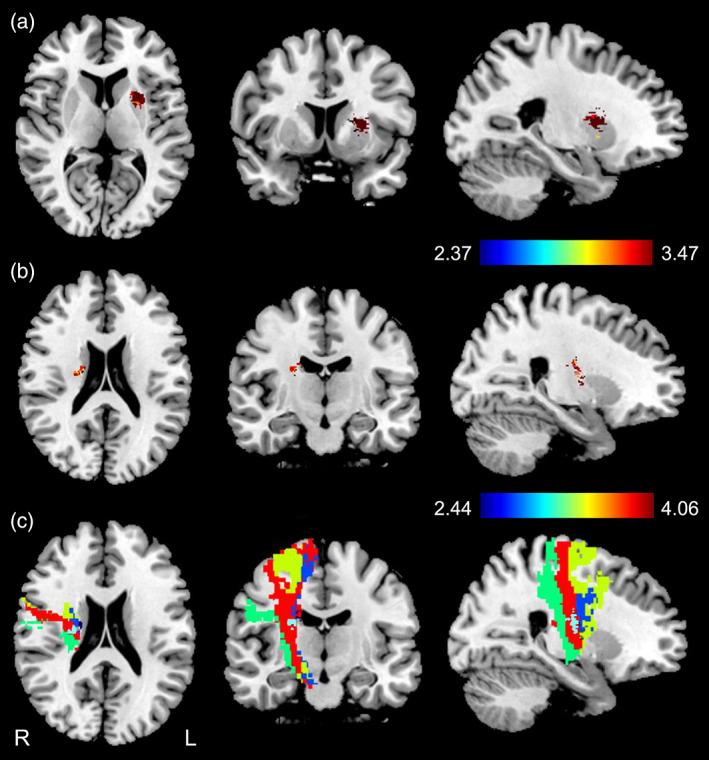

Subcortical ischemic stroke can lead to persistent structural changes in the cerebral cortex. The evolution of cortical structural changes after subcortical stroke is largely unknown, as are their relations with motor recovery, lesion location, and early impairment of specific subsets of fibers in the corticospinal tract (CST). In this observational study, cortical structural changes were compared between 181 chronic patients with subcortical stroke involving the motor pathway and 113 healthy controls. The impacts of acute lesion location and early impairments of specific CSTs on cortical structural changes were investigated in the patients by combining voxel-based correlation analysis with an association study that compared CST damage and cortical structural changes. Longitudinal patterns of cortical structural change were explored in a group of 81 patients with subcortical stroke using a linear mixed-effects model. In the cross-sectional analyses, patients with partial recovery showed more significant reductions in cortical thickness, surface area, or gray matter volume in the sensorimotor cortex, cingulate gyrus, and gyrus rectus than did patients with complete recovery; however, patients with complete recovery demonstrated more significant increases in the cortical structural measures in frontal, temporal, and occipital regions than did patients with partial recovery. Voxel-based correlation analysis in these patients showed that acute stroke lesions involving the CST fibers originating from the primary motor cortex were associated with cortical thickness reductions in the ipsilesional motor cortex in the chronic stage. Acute stroke lesions in the putamen were correlated with increased surface area in the temporal pole in the chronic stage. The early impairment of the CST fibers originating from the primary sensory area was associated with increased cortical thickness in the occipital cortex. In the longitudinal analyses, patients with partial recovery showed gradually reduced cortical thickness, surface area, and gray matter volume in brain regions with significant structural damage in the chronic stage. Patients with complete recovery demonstrated gradually increasing cortical thickness, surface area, and gray-matter volume in the frontal, temporal, and occipital regions. The directions of slow structural changes in the frontal, occipital, and cingulate cortices were completely different between patients with partial and complete recovery. Complex cortical structural changes and their dynamic evolution patterns were different, even contrasting, in patients with partial and complete recovery, and were associated with lesion location and with impairment of specific CST fiber subsets.

皮质下缺血性卒中可导致大脑皮层持续的结构性改变。皮质下卒中后皮质结构变化的演变在很大程度上是未知的,其与运动恢复、病变部位以及皮质脊髓束(CST)中特定纤维亚群的早期损伤的关系也未知。在这项观察性研究中,比较了 181 例涉及运动通路的皮质下卒中慢性患者和 113 例健康对照者之间的皮质结构变化。通过将体素相关分析与关联研究相结合,研究了患者急性病变部位和 CST 特定亚群的早期损伤对皮质结构变化的影响,在关联研究中比较了 CST 损伤和皮质结构变化。使用线性混合效应模型对一组 81 例皮质下卒中患者进行了皮质结构变化的纵向研究。在横断面分析中,部分恢复的患者较完全恢复的患者在感觉运动皮层、扣带回和直回的皮质厚度、表面积或灰质体积减少更显著;然而,完全恢复的患者在额、颞和枕叶的皮质结构测量值的增加更显著。这些患者的体素相关分析显示,起源于初级运动皮层的 CST 纤维的急性卒中病变与慢性阶段对侧运动皮层的皮质厚度减少有关。壳核的急性卒中病变与慢性阶段颞极的表面积增加有关。起源于初级感觉区的 CST 纤维的早期损伤与枕叶皮质的皮质厚度增加有关。在纵向分析中,部分恢复的患者在慢性阶段有显著结构损伤的脑区表现出逐渐减少的皮质厚度、表面积和灰质体积。完全恢复的患者在额、颞和枕叶区域表现出逐渐增加的皮质厚度、表面积和灰质体积。部分和完全恢复患者的额、枕和扣带回皮质的慢结构变化方向完全不同。部分和完全恢复患者的皮质结构变化复杂,且其动态演变模式不同,甚至相互矛盾,这与病变部位和特定 CST 纤维亚群的损伤有关。